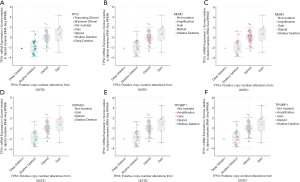

Different mutation types may have distinct biological functions in various cancers, and the co-expression of genes may also affect gene functions. Using the cBioPortal database, we explored the location and types of mutation, as well as co-expression, among genes related to the TP53 signaling pathway. Among these genes, TP53 (2.3%) was the most frequently aberrant gene in WT, followed by MDM4 (0.8%), and then MDM2 and TP53BP1 (0.2%). The most common types of mutation in TP53 were missense and deep deception, while amplification was the most common mutation in MDM2, MDM4, and TP53BP1 (Figure 3A,B). The three-dimensional structure of TP53 is shown in Figure 3C.

The location of mutations in TP53 are shown in Figure 4. The significant co-expressed genes in the TP53 signaling pathway included ZNF609 (zinc finger protein 609), WRAP53 (WD40-encoding RNA antisense to p53), CNOT2 (CC chemokine receptor 4-negative regulator of transcription 2), ANGEL2, TMEM255A, and CDH13 (cadherin 13) (Figure 5). Further, we investigated the relationships of the mutation types (Figure 6), copy number alterations (CAN, Figure 7), and methylation (Figure 8) with the expression levels of defined genes. The gene expression levels were negatively correlated with methylation, but the CNA and mutated type did not have a significant influence. Figure 9 shows the relationship between the genes in the TP53 signaling pathway.